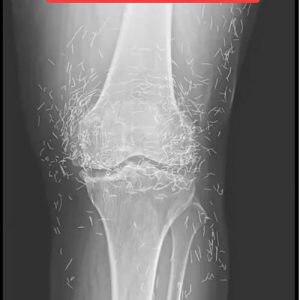

When doctors reviewed the X-ray scans of a 65-year-old woman from South Korea who had been suffering from intense and chronic knee pain, they stumbled upon a shocking discovery that seemed almost surreal….